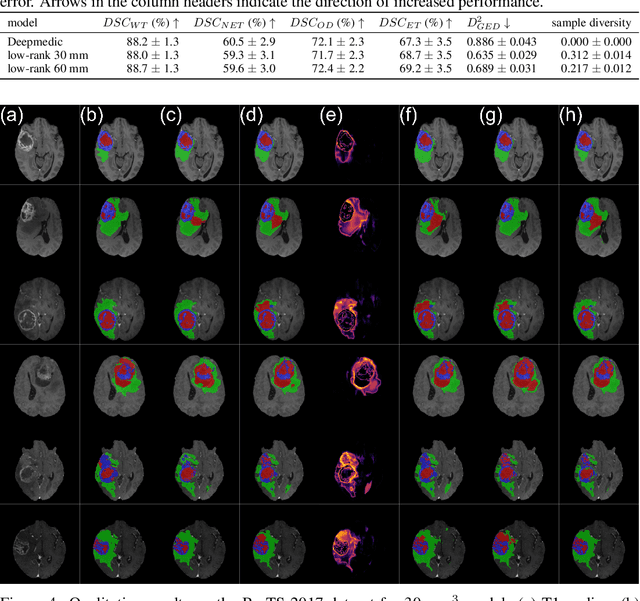

Abstract:In image segmentation, there is often more than one plausible solution for a given input. In medical imaging, for example, experts will often disagree about the exact location of object boundaries. Estimating this inherent uncertainty and predicting multiple plausible hypotheses is of great interest in many applications, yet this ability is lacking in most current deep learning methods. In this paper, we introduce stochastic segmentation networks (SSNs), an efficient probabilistic method for modelling aleatoric uncertainty with any image segmentation network architecture. In contrast to approaches that produce pixel-wise estimates, SSNs model joint distributions over entire label maps and thus can generate multiple spatially coherent hypotheses for a single image. By using a low-rank multivariate normal distribution over the logit space to model the probability of the label map given the image, we obtain a spatially consistent probability distribution that can be efficiently computed by a neural network without any changes to the underlying architecture. We tested our method on the segmentation of real-world medical data, including lung nodules in 2D CT and brain tumours in 3D multimodal MRI scans. SSNs outperform state-of-the-art for modelling correlated uncertainty in ambiguous images while being much simpler, more flexible, and more efficient.